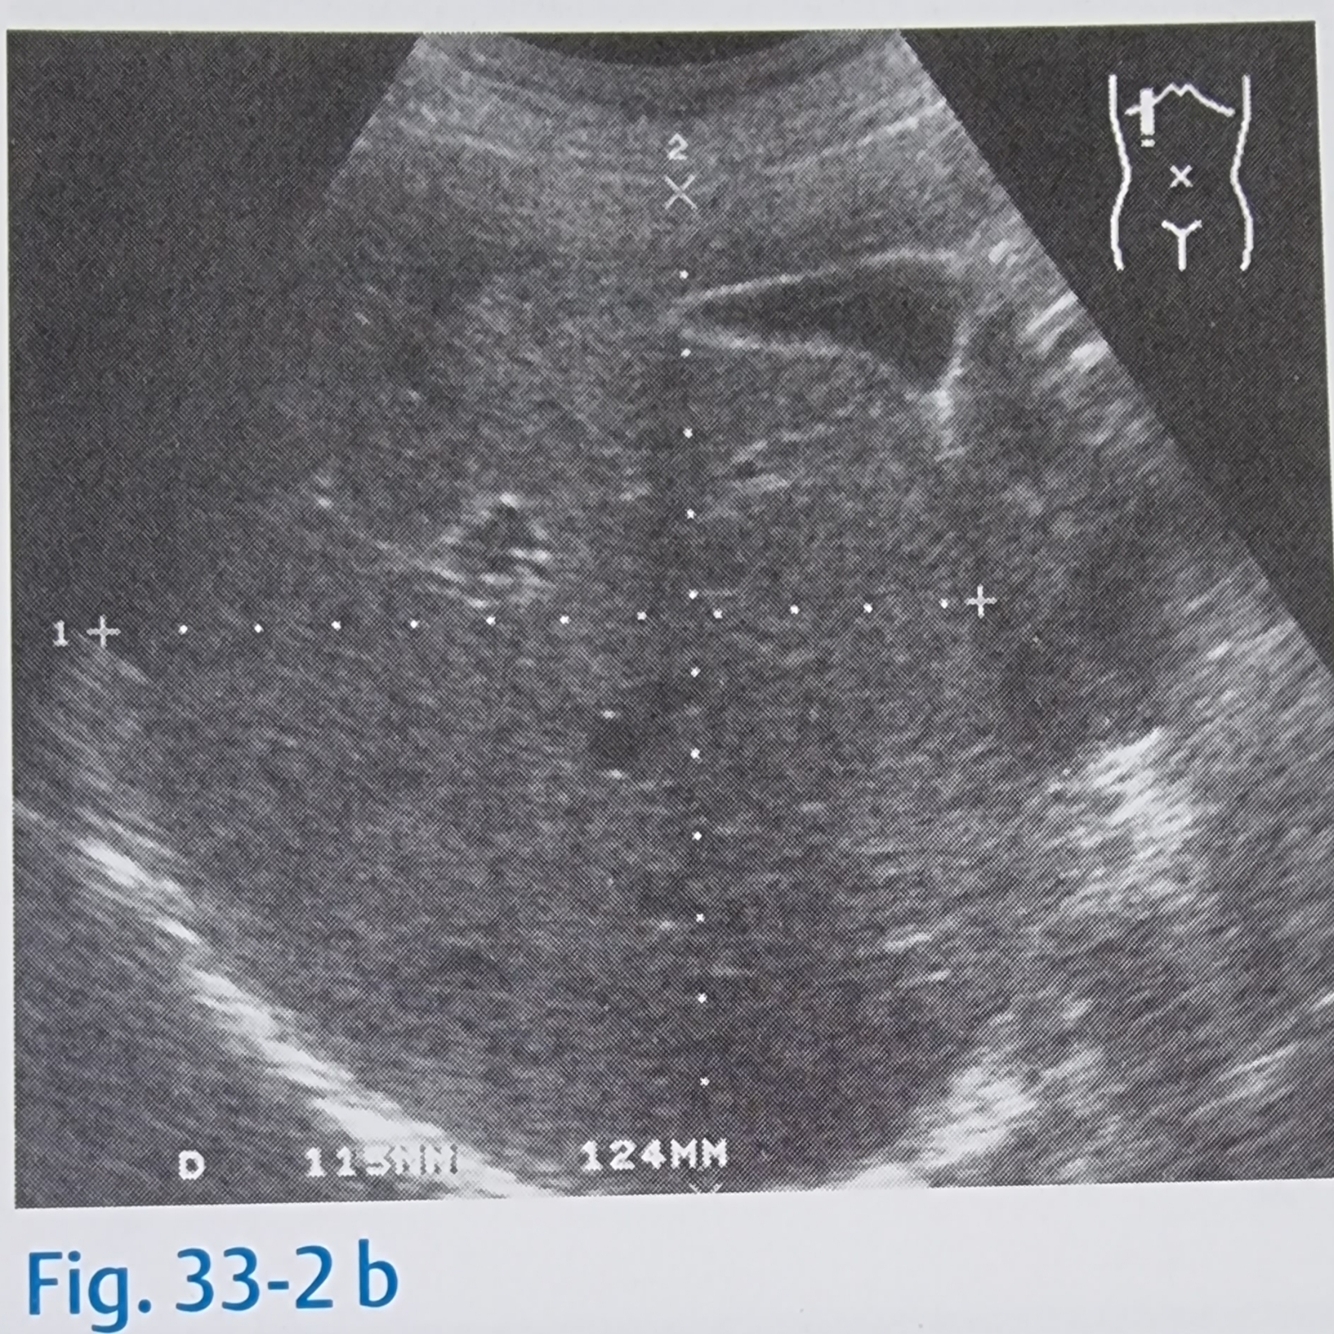

Apesar de pouco utilizado nos dias de hoje, a determinação do tamanho do fígado era utilizado medindo na LMC direita o diâmetro crânio caudal e ventrodorsal do fígado, qual o valor médio normal crânio caudal normal?

A

O diâmetro normal nos adultos oscila entre 11cm e 15cm